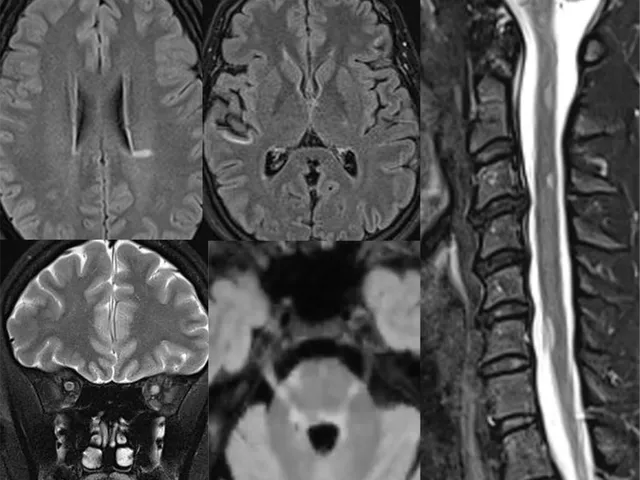

This training is accredited by EACCME with 9 CME credits This intensive 3-day MRI course is designed to enhance your expertise in the use of MRI for diagnosing and monitoring multiple sclerosis (MS) and other inflammatory demyelinating disorders of the central nervous system, such as NMOSD and MOGAD.

The course combines lectures, hands-on MRI case studies, and group discussions to provide a comprehensive understanding of these complex conditions.

- Lectures on reading brain and spinal cord MRI for diagnosing multiple sclerosis and other inflammatory-demyelinating disorders of the central nervous system.